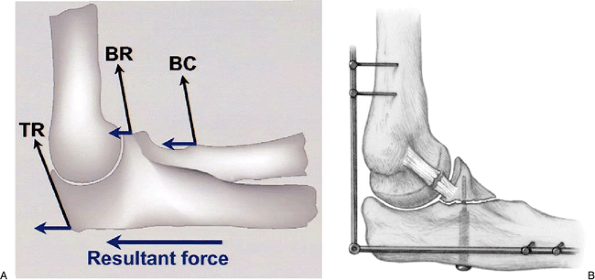

and extend the elbow joint (Fig. 7-4). The

device allows motion of the ulnohumeral joint while placing a distal

distraction force on the ulna, thus protecting the articulation. The

distraction device

is maintained for 3 to 6 weeks, depending upon the nature of the injury (1) (see Chapter 8).

Figure 7-4.

Complex instability of the elbow. Posterior directed forces occur from the posteriorly directed pull of the biceps, brachialis, and triceps (A). If fixation is inadequate, neutralization of coronoid fixation is carried out with an external fixator (B). |